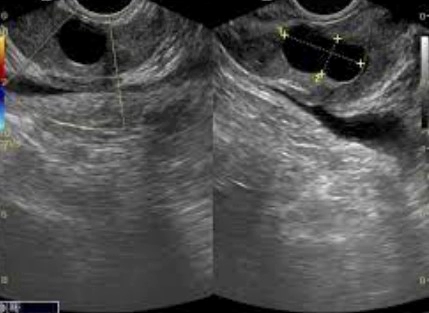

낭종이 클 경우, 미세 침습 수술이 선택될 수 있습니다. 이러한 수술은 초음파, 컴퓨터 토모그래피 (CT) 스캔, 자기 공명 영상 (MRI) 등의 가이드 하에 수행됩니다. 이 과정에서 의사는 작은 침을 통해 낭종으로 가는 길을 만들고, 그 후에 이 침을 통해 낭종에 들어가 액체를 배출합니다. 이렇게 하면 낭종의 크기가 줄어들고 증상이 완화됩니다.